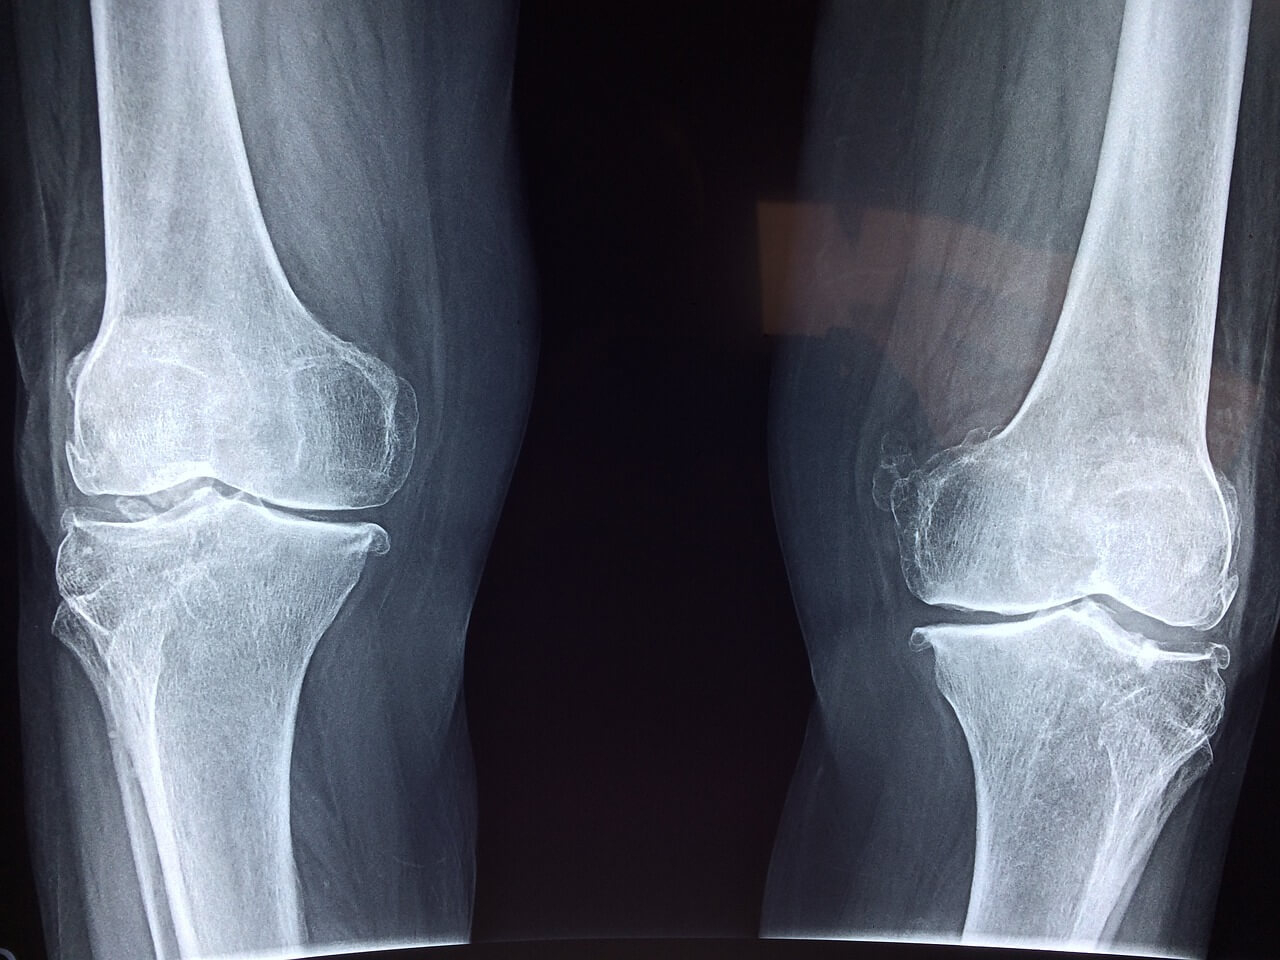

Solitamente, ginocchia e caviglie sono fra le articolazioni maggiormente interessate dalla malattia, ma in realtà l’AIG può colpire tutte le articolazioni del corpo. In alcuni casi, la malattia può interessare “poche” articolazioni (artrite idiopatica giovanile oligoarticolare) e può manifestarsi entro i primi 6 mesi di vita, soprattutto nelle bambine.

Non esistono attualmente degli esami specifici che permettano di individuare immediatamente l’artrite idiopatica giovanile. La diagnosi si basa in primis sull’esame dei sintomi manifestati dai giovani pazienti, quindi verranno eseguiti dei test di imaging e analisi di laboratorio, visite oculistiche ed esami articolari.

Fra i test diagnostici attualmente impiegati rientrano la radiografia, la risonanza magnetica e l’ecografia articolare.